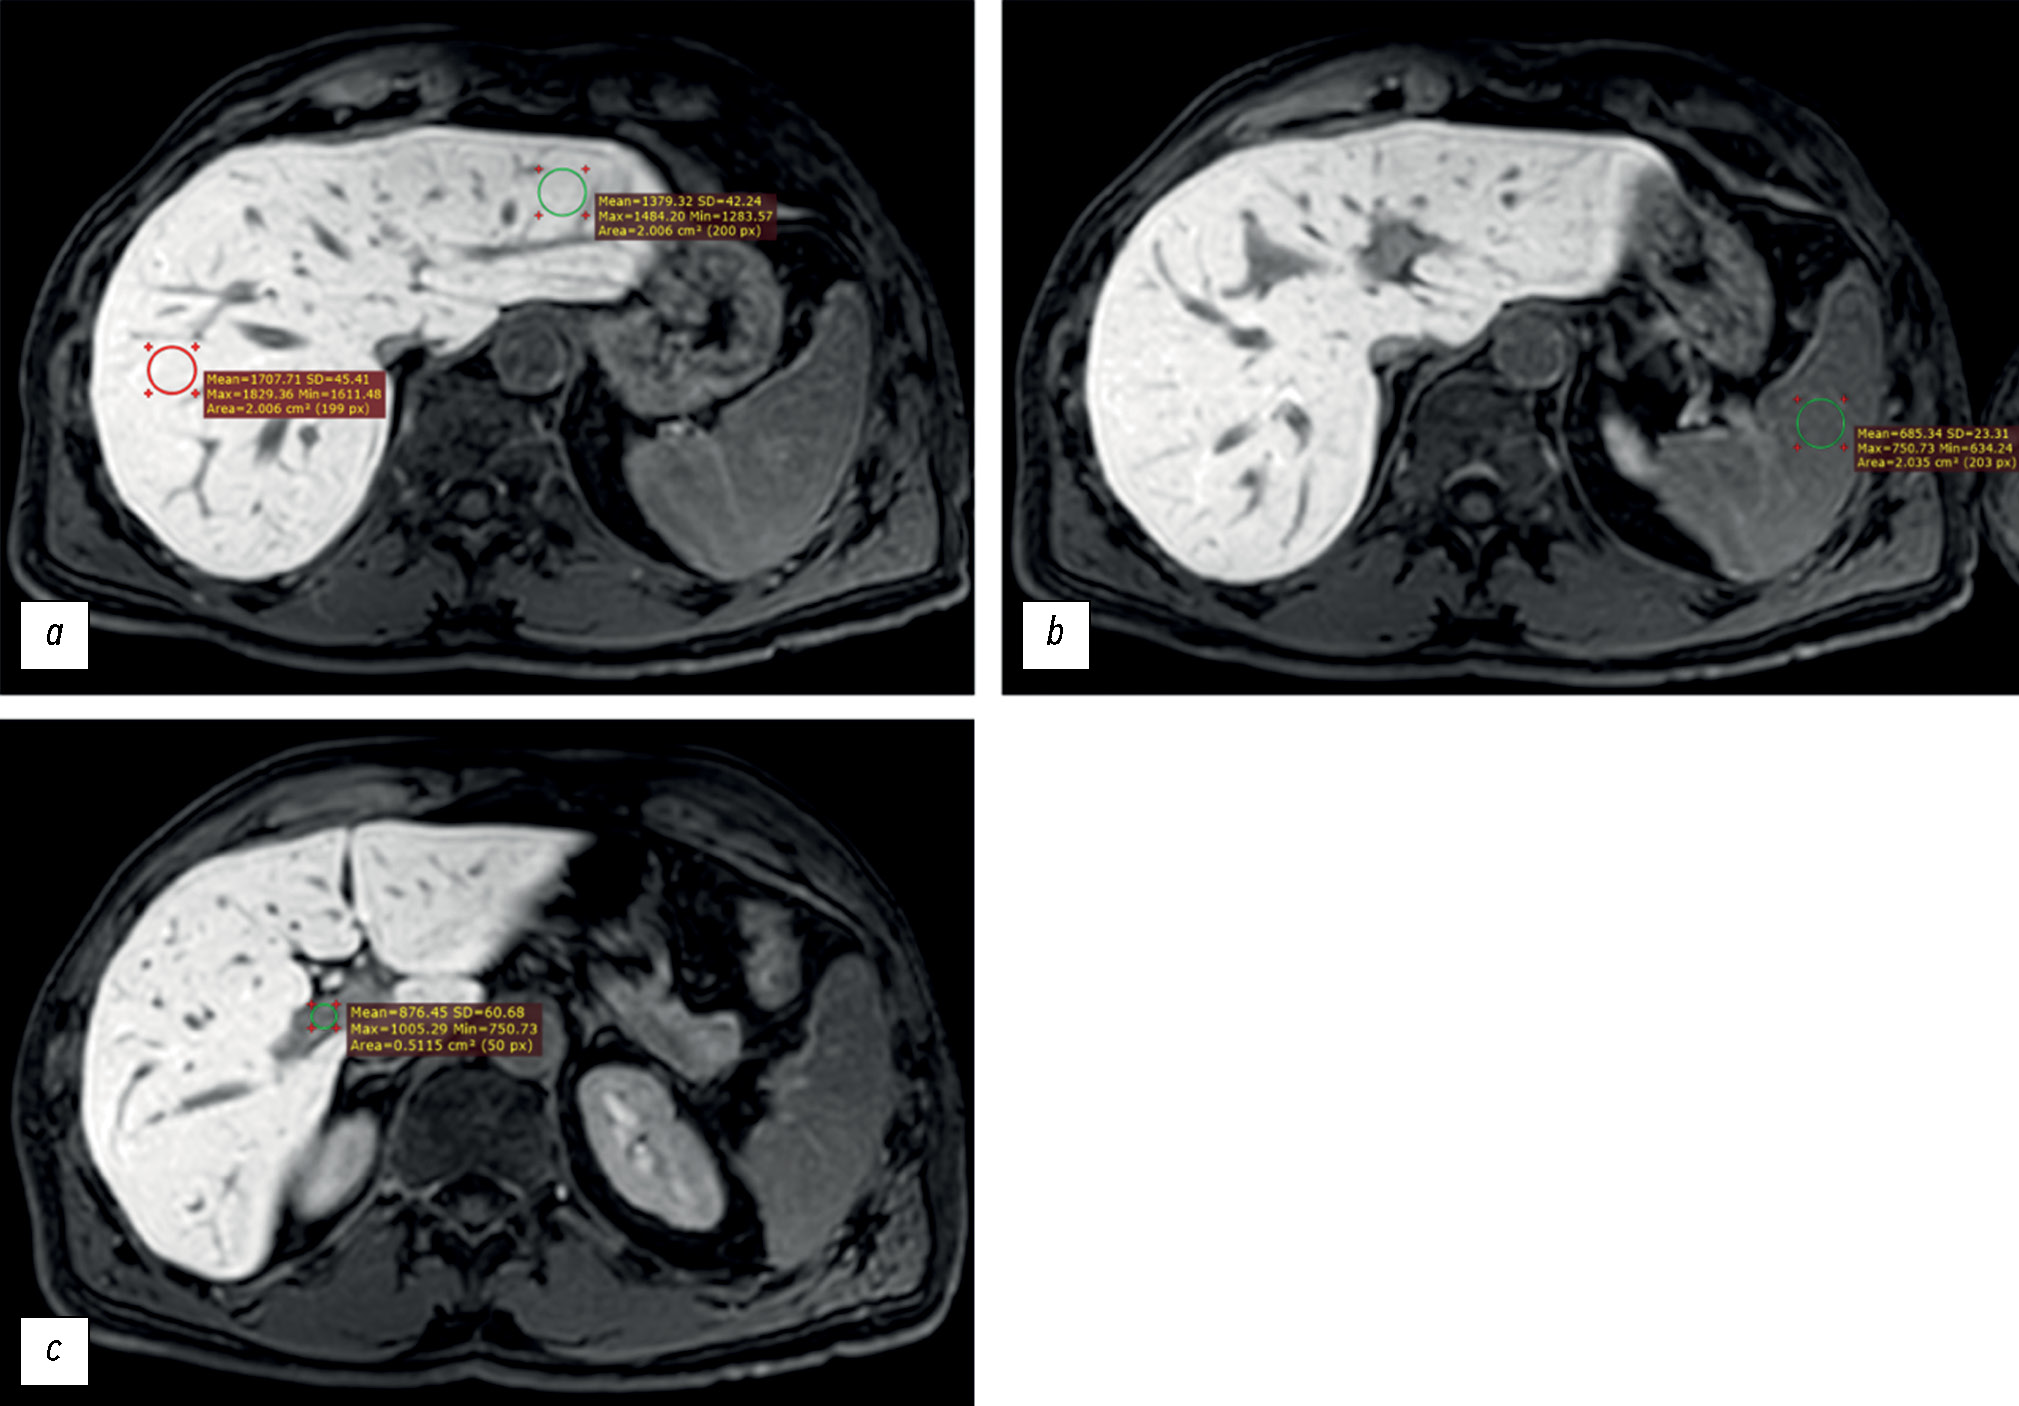

BACKGROUND: Liver function assessment is very important in clinical practice. The use of magnetic resonance imaging for the anatomical and functional evaluation of the liver is possible in actual clinical practice.

AIM: To examine the possibility of using hepatobiliary contrast-enhanced magnetic resonance imaging for the evaluation of liver function.

MATERIALS AND METHODS: Datasets of patients who underwent gadoxetic acid-enhanced magnetic resonance imaging were retrospectively reviewed. Patients were divided into two groups: group 1 included patients with impaired liver function, and group 2 included those with normal liver function. Based on magnetic resonance imaging in the hepatobiliary phase, the liver parenchyma signal intensity and its ratio to spleen signal intensity and portal vein signal intensity were estimated. Differences among these parameters were compared between groups. The correlation between liver parenchyma signal intensity and laboratory blood tests reflecting liver function (total bilirubin, albumen, aspartate aminotransferase, alanine aminotransferase, alkaline phosphatase, gamma glutamyl transpeptidase, and prothrombin time) were analyzed.

RESULTS: Datasets of 53 patients (25 men and 28 women, aged 24–84 years) were analyzed. Group 1 included 19 patients, whereas group 2 included 34. The median liver parenchyma signal intensity was 919.05 [669.65; 1258.35] in group 1 and 1525.13 [1460.5; 1631.4] in group 2 (p=0.0000001). The median ratio of liver parenchyma signal intensity to spleen signal intensity was 1.2 [1.04;1.7] in group 1 and 1.7 [1.46; 1.96] in group 2 (p=0.00076). The median ratio of liver parenchyma signal intensity to portal vein signal intensity was 1.44 [1.29; 1.83] in group 1 and 1.6 [1.43; 1.83] in group 2 (p=0.1). The estimated correlation values between liver parenchyma signal intensity and blood tests parameters were as follows: total bilirubin (r=–0.61; p=0.000001), albumen (r=0.13; p=0.61), aspartate aminotransferase (r=–0.57; p=0.000009), alanine aminotransferase (r=–0.44; p=0.001), alkaline phosphatase (r=–0.45; p=0.0007), gamma glutamyl transpeptidase (r=–0.5; p=0.0003), prothrombin time (r=–0.34; p=0.04).

CONCLUSION: The study reflects the ability to assess liver function using indices (liver parenchyma signal intensity and its ratio to spleen signal intensity) derived from gadoxetic acid-enhanced magnetic resonance imaging. However, this study did not confirm the assumed effectiveness of using the liver parenchyma signal intensity to portal vein signal intensity ratio as an index of liver function. A significant inverse correlation was identified between liver parenchyma signal intensity and blood test parameters in reflecting liver function, except for albumin. The results indicate the possibility of using magnetic resonance imaging to assess liver function.